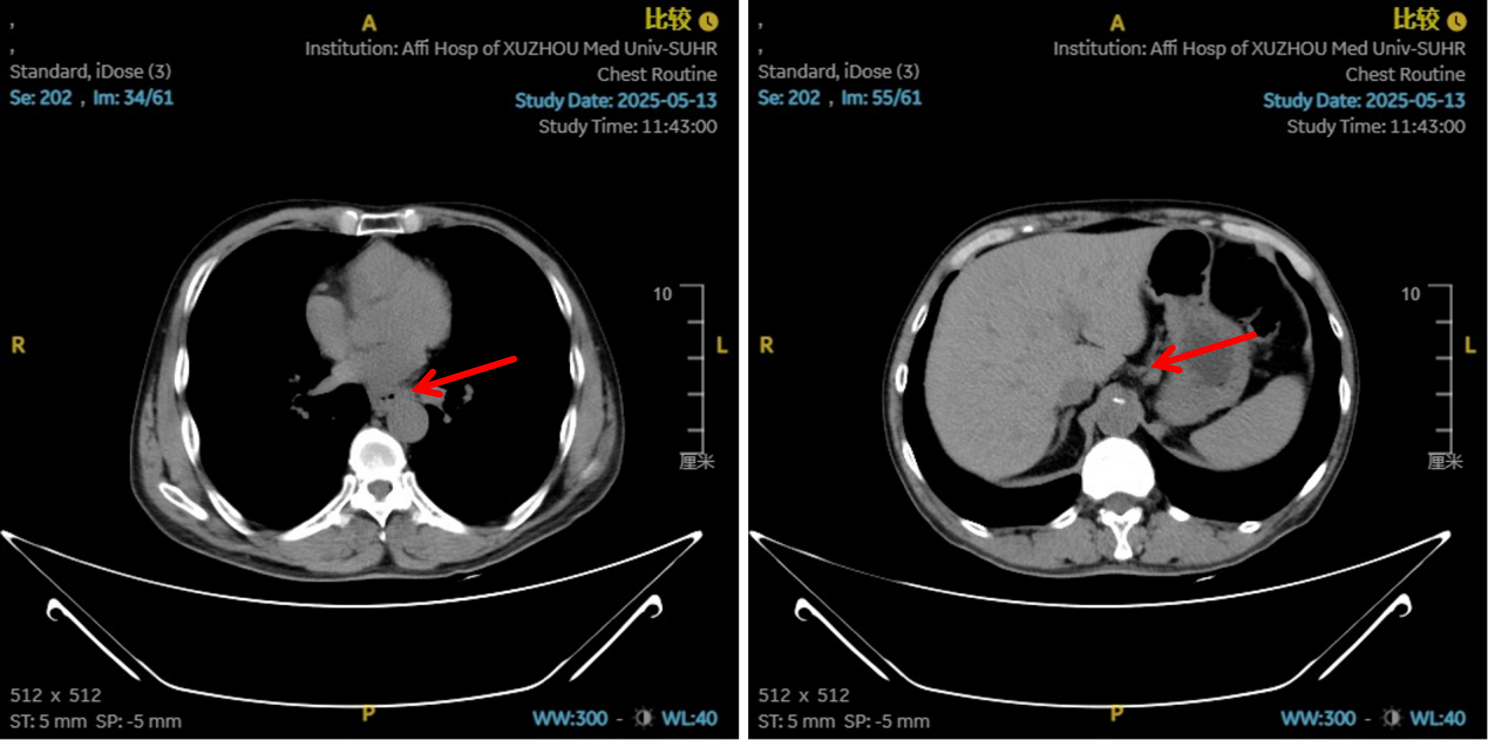

2. 巩固与协同治疗(第3-6周期):

方案:在原有方案基础上联合PD-1抑制剂(紫杉醇聚合物胶束300mg+洛铂40mg+重组人血管内皮抑制素210mg+信迪利单抗200mg)。在化疗造成肿瘤细胞大量死亡、释放抗原的同时,联合PD-1抑制剂,解除T细胞抑制,激活全身性、长效的抗肿瘤免疫应答。

图5:4、6周期化免靶后食管癌病灶对比

图6:4、6周期化免靶后淋巴结对比

图7:4周期治疗后影像学 [图左:“食管Ca化疗后”,食管胸中下段管壁增厚,较厚处管壁约12mm,边缘模糊,病灶局部与邻近大血管、气管壁分界不清。图右:纵隔内(3P、4、7)、左肺门示稍大淋巴结影。]

图8:6周期治疗后影像学 [图左:“食管Ca化疗后”,食管胸中下段管壁增厚,较厚处管壁约10mm,边缘模糊,病灶局部与邻近大血管、气管壁分界不清。图右:纵隔内(3P、4、7)示小淋巴结影。]

疗效评估

治疗2周期后,食管壁厚度由17mm降至15mm,淋巴结由18mm×15mm缩小至16mm×13mm;4周期后,食管壁进一步缩至12mm,淋巴结明显减少;6周期后,食管壁仅余10mm,纵隔内仅见小淋巴结影,疗效评估“接近CR”。